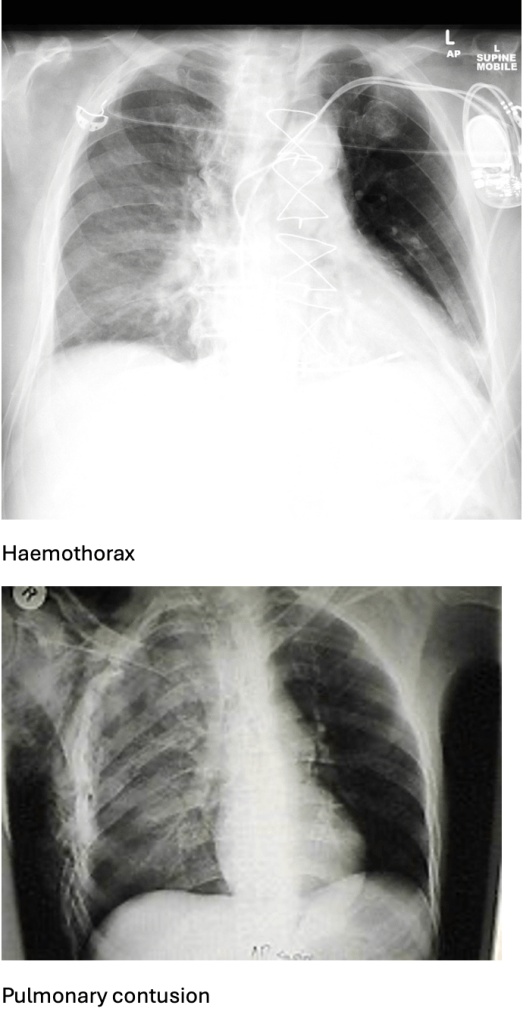

Answer: B) Pulmonary contusion

Explanation: A pulmonary contusion occurs after direct impact to the chest compresses lung tissue. This causes rupture of alveolar capillaries and bleeding into the alveoli. The resulting inflammatory response leads to oedema and accumulation of blood in the lung parenchyma. Clinical features include dyspnoea, haemoptysis, and crackles.

D) is incorrect as haemothorax usually presents with dullness to percussion and evidence of fluid on X-ray. Infiltrates indicate alveolar injury, not fluid collection.

C) is incorrect as haemothorax is characterised by dullness to percussion and an opacity on X-ray due to blood accumulation.

D) is incorrect as pulmonary contusion causes patchy infiltrates on X-ray and often follows blunt trauma with no pleural space involvement.